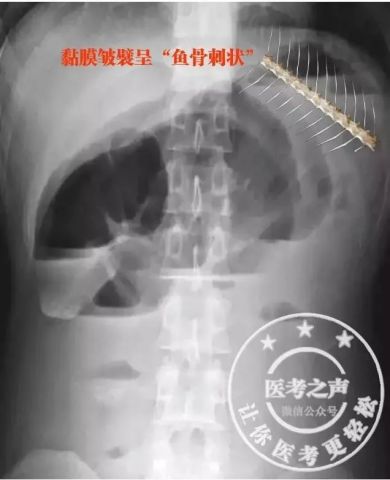

五、大肠疾病 1. 溃疡性结肠炎(ulcerative